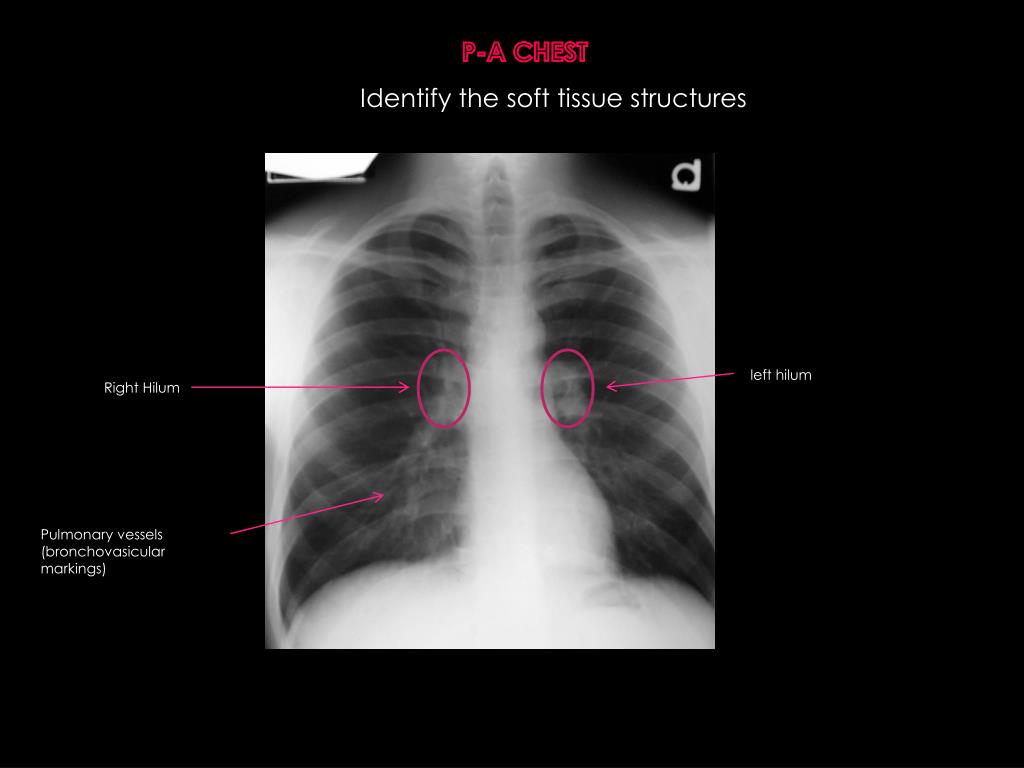

10. P-A CHEST Identify the soft tissue structures left hilum RightHilum Pulmonary vessels (bronchovasicular markings)